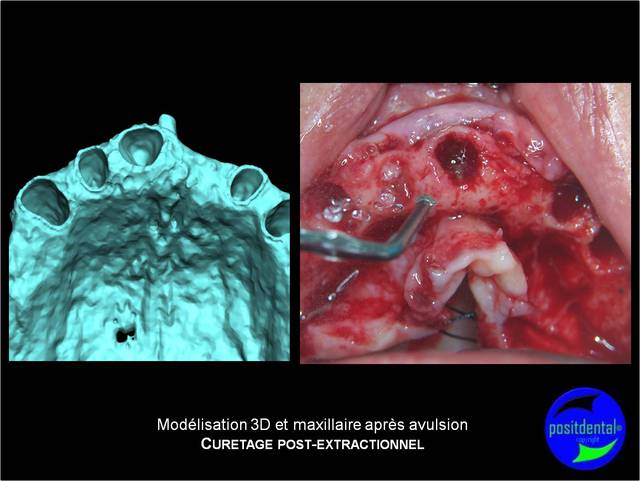

Mise en Charge Immédiate Post Extractionnelle , MCIPE partie chirurgicale de A à Z

implants in situ et S.I.A.O pré-opératoire